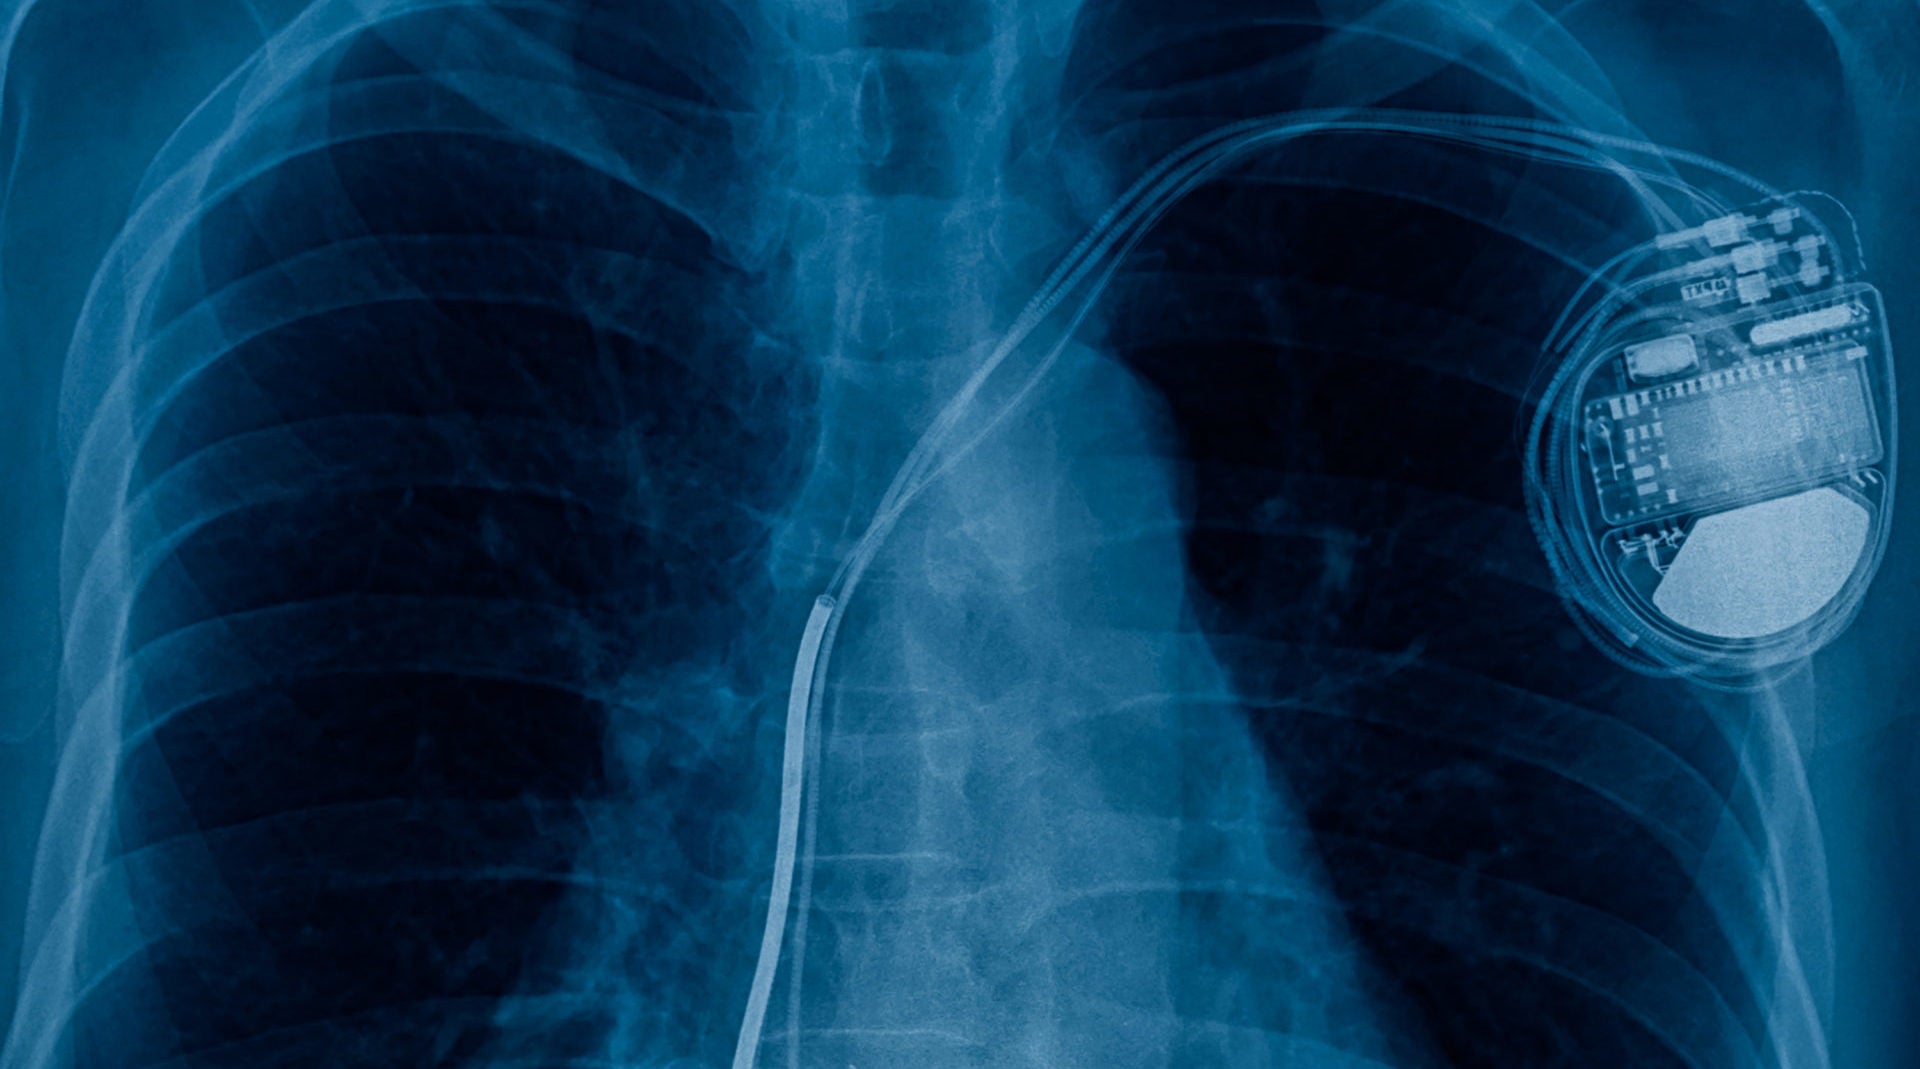

Researchers have created artificial intelligence (AI) software that identifies the make and model of cardiac rhythm devices – such as pacemakers – in seconds, massively speeding up treatment times in potentially life-threatening conditions.

Although rare, a cardiac device can malfunction, leading to heart palpitations, loss of consciousness or electric shocks. In the absence of patient records or the patient knowing the type of device, doctors currently use a flowchart algorithm to identify pacemakers via a process of elimination.

To combat this, a research team at Imperial College London, UK, developed AI software that recognises the make and model of a cardiac device from an X-ray image alone.

After uploading the image to a computer, the AI program detects the type of device within seconds, which means patients can be diagnosed and treated at a much faster rate.

Because it can identify over 1,600 different types of cardiac devices, it would have had to be trained on many times this amount of images, with slight variations of each device.

When the team tested the software on over 1,500 radiographic images from patients at Hammersmith Hospital between 1998 and 2018, they found the software outperformed traditional identification methods.

Where the current flowchart method was accurate for 72% of the time, the Imperial College London software was 99% accurate.